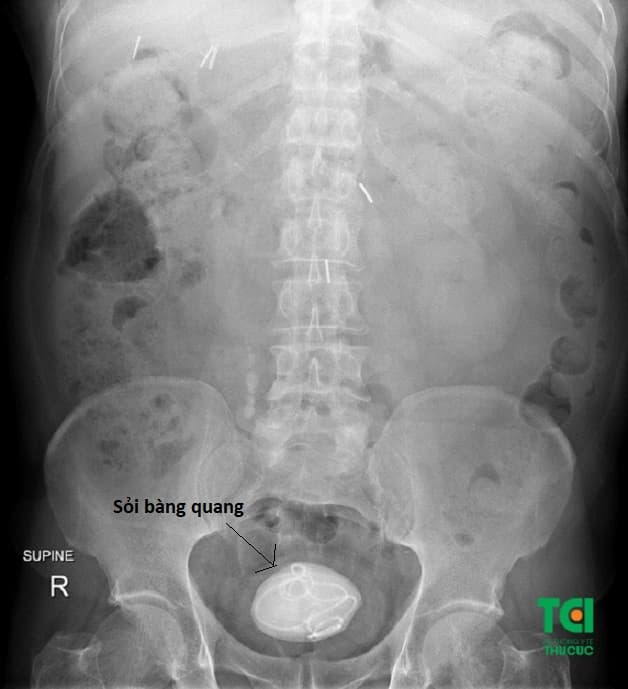

Sỏi bàng quang là một dạng sỏi tiết niệu khá phổ biến được hình thành do quá trình ứ đọng nước tiểu lâu ngày tại bàng quang, tạo điều kiện cho quá trình lắng cặn, kết tinh và hình thành sỏi. Hoặc cũng do nguyên nhân sỏi đường tiết niệu phía trên rơi xuống và mắc kẹt tại bàng quang không di chuyển được ra ngoài.

Người mắc sỏi bàng quang có thể dễ bỏ lỡ những dấu hiệu nhận biết bệnh khi sỏi mới hình thành, sỏi kích thước còn nhỏ. Hoặc có thể do tâm lý lo lắng đến bệnh viện điều trị, sợ mổ. Do vậy cũng có khá nhiều người đến viện và được xác định mắc sỏi bàng quang kích thước khủng lên đến vài centimet. Lúc này người bệnh đã bỏ lỡ mất thời điểm vàng để thực hiện điều trị bằng các biện pháp điều trị nhẹ nhàng, xâm lấn tối thiểu và phải tiếp nhận mổ sỏi bàng quang.

Bệnh nhân có sỏi bàng quang kích thước khủng được chỉ định mổ mở lấy sỏi tại Thu Cúc TCI